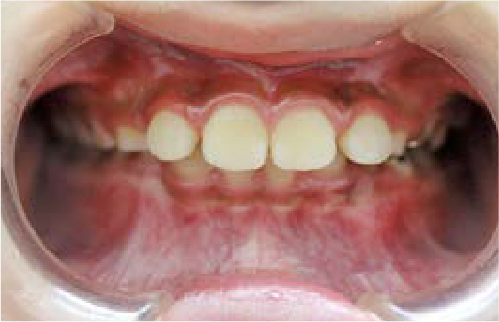

ガタガタな歯並びに悩むも…抜かずに治す選択

Kさん (矯正開始時:8歳)

Before

After

前歯のすき間や歯並びの乱れが見られ、普段の生活の中で、無意識に舌を押しつけるクセや飲み込み方のクセが確認されました。

治療を終えて

装置をしっかり使うことで、あごの位置が整い、舌の正しい位置や動きが戻り、ほっぺたやくちびるの筋肉の使い方も改善されました。その結果、歯並びが整いお口の機能も良くなりました。もちろん非抜歯での治療です。

主訴・治療内容 他院で抜歯のうえ、ブラケット矯正を勧められたが、できれば歯を抜かずに治療したいとの要望で来院されました。

治療期間 5年4ヶ月

費用 495,000円(税込)